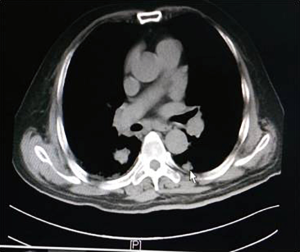

As illustrated in Table 3, tumors were significantly reduced in all 6 patients after the implantation of radioactive particles. A typical case can be seen in Figures 4,5.

As shown in Figure 7 and Figure 3, there were 2 CRs and 4 PRs after follow-up for 1 month, indicating a response rate (RR) of 6/6, and a disease control rate (DCR) of 6/6; six patients were followed up for 6 months, including one patient who refused follow-up visit (still alive),while the other 5 patients were followed up regularly, including 3 CRs and 2 PRs; five patients were followed up for 12 months, including 3 CRs, 1 PR and 1 PD, indicating an RR of 4/5, a DCR of 4/5, and a progression rate of 1/5; four patients were followed up for 18 months, including 3 CRs and 1 SD, indicating a RR of 3/4 and a DCR of 4/4; four patients were followed up for 24 months, including 1 patient who refused a follow-up visit (still alive), while the other 3 patients were still followed up regularly; there were still 4 patients who were followed up for 30 months, including 1 patient who refused follow-up visit (alive) and 3 patients who were followed up on a regular basis; one patient was followed up for 36 months and had a recurrence of primary lesion, with the response being evaluated as PD. In addition, Figure 7 shows that patient E achieved significant response after implantation of 125I particles, and the response was evaluated as CR 1 month after implantation (Figures 8,9); however, the primary lesion recurred and was enlarged with left lung metastasis in month 12 (Figures 10,11), whereupon the response was evaluated as PD. The patient was given CT-guided implantation of 125I radioactive particles again for treatment of the recurrent lesion. The repeated pulmonary CT after re-implantation showed significant reduction of tumor (reduction rate 27.32%), as shown in Figure 12, and the response was subsequently re-evaluated as SD.

Other relevant studies have shown a unique advantage of implantation of radioactive particles in the treatment of lung cancer. In a study by Lu et al. (10), 15 patients with obstructive pneumonia caused by central type lung cancer were given a bronchoscopic implantation of 125I radioactive particles, and followed up in months 2, 6, 12, 18 and 24 after implantation. The median survival was 15.6 months, and the one-year lung recruitment rate was 80.0%, which significantly improved the quality of life. To compare, in our study’s response evaluation from regular follow-up of patients who received the CT-guided implantation of radioactive 125I, it was found that the tumors had significantly shrunk in all 6 patients. Typical cases are illustrated in Figures 4 and 5, and as can be seen in Figure 6, the most obvious reduction of tumor was seen in the 6th month of follow-up. In the 5 patients who were followed up, there were 3 CRs, indicating an RR of 5/5 (100%) and a DCR of 5/5 (100%). This shows that the implantation of radioactive particle achieved the best response within 6 months in the treatment of early lung cancer. In addition, as Figure 3 shows, 5 patients were followed up 1 year after implantation and had a survival rate of 5/5 (100%), 4 patients were followed up 2 years after implantation and had a survival rate of 4/4 (100%), and the longest time after enrollment was up to 3 years and 5 months; at the time of writing, this patient is still alive. The observations above demonstrate the significant efficacy of the implantation of 125I radioactive particles in treatment of early lung cancer.